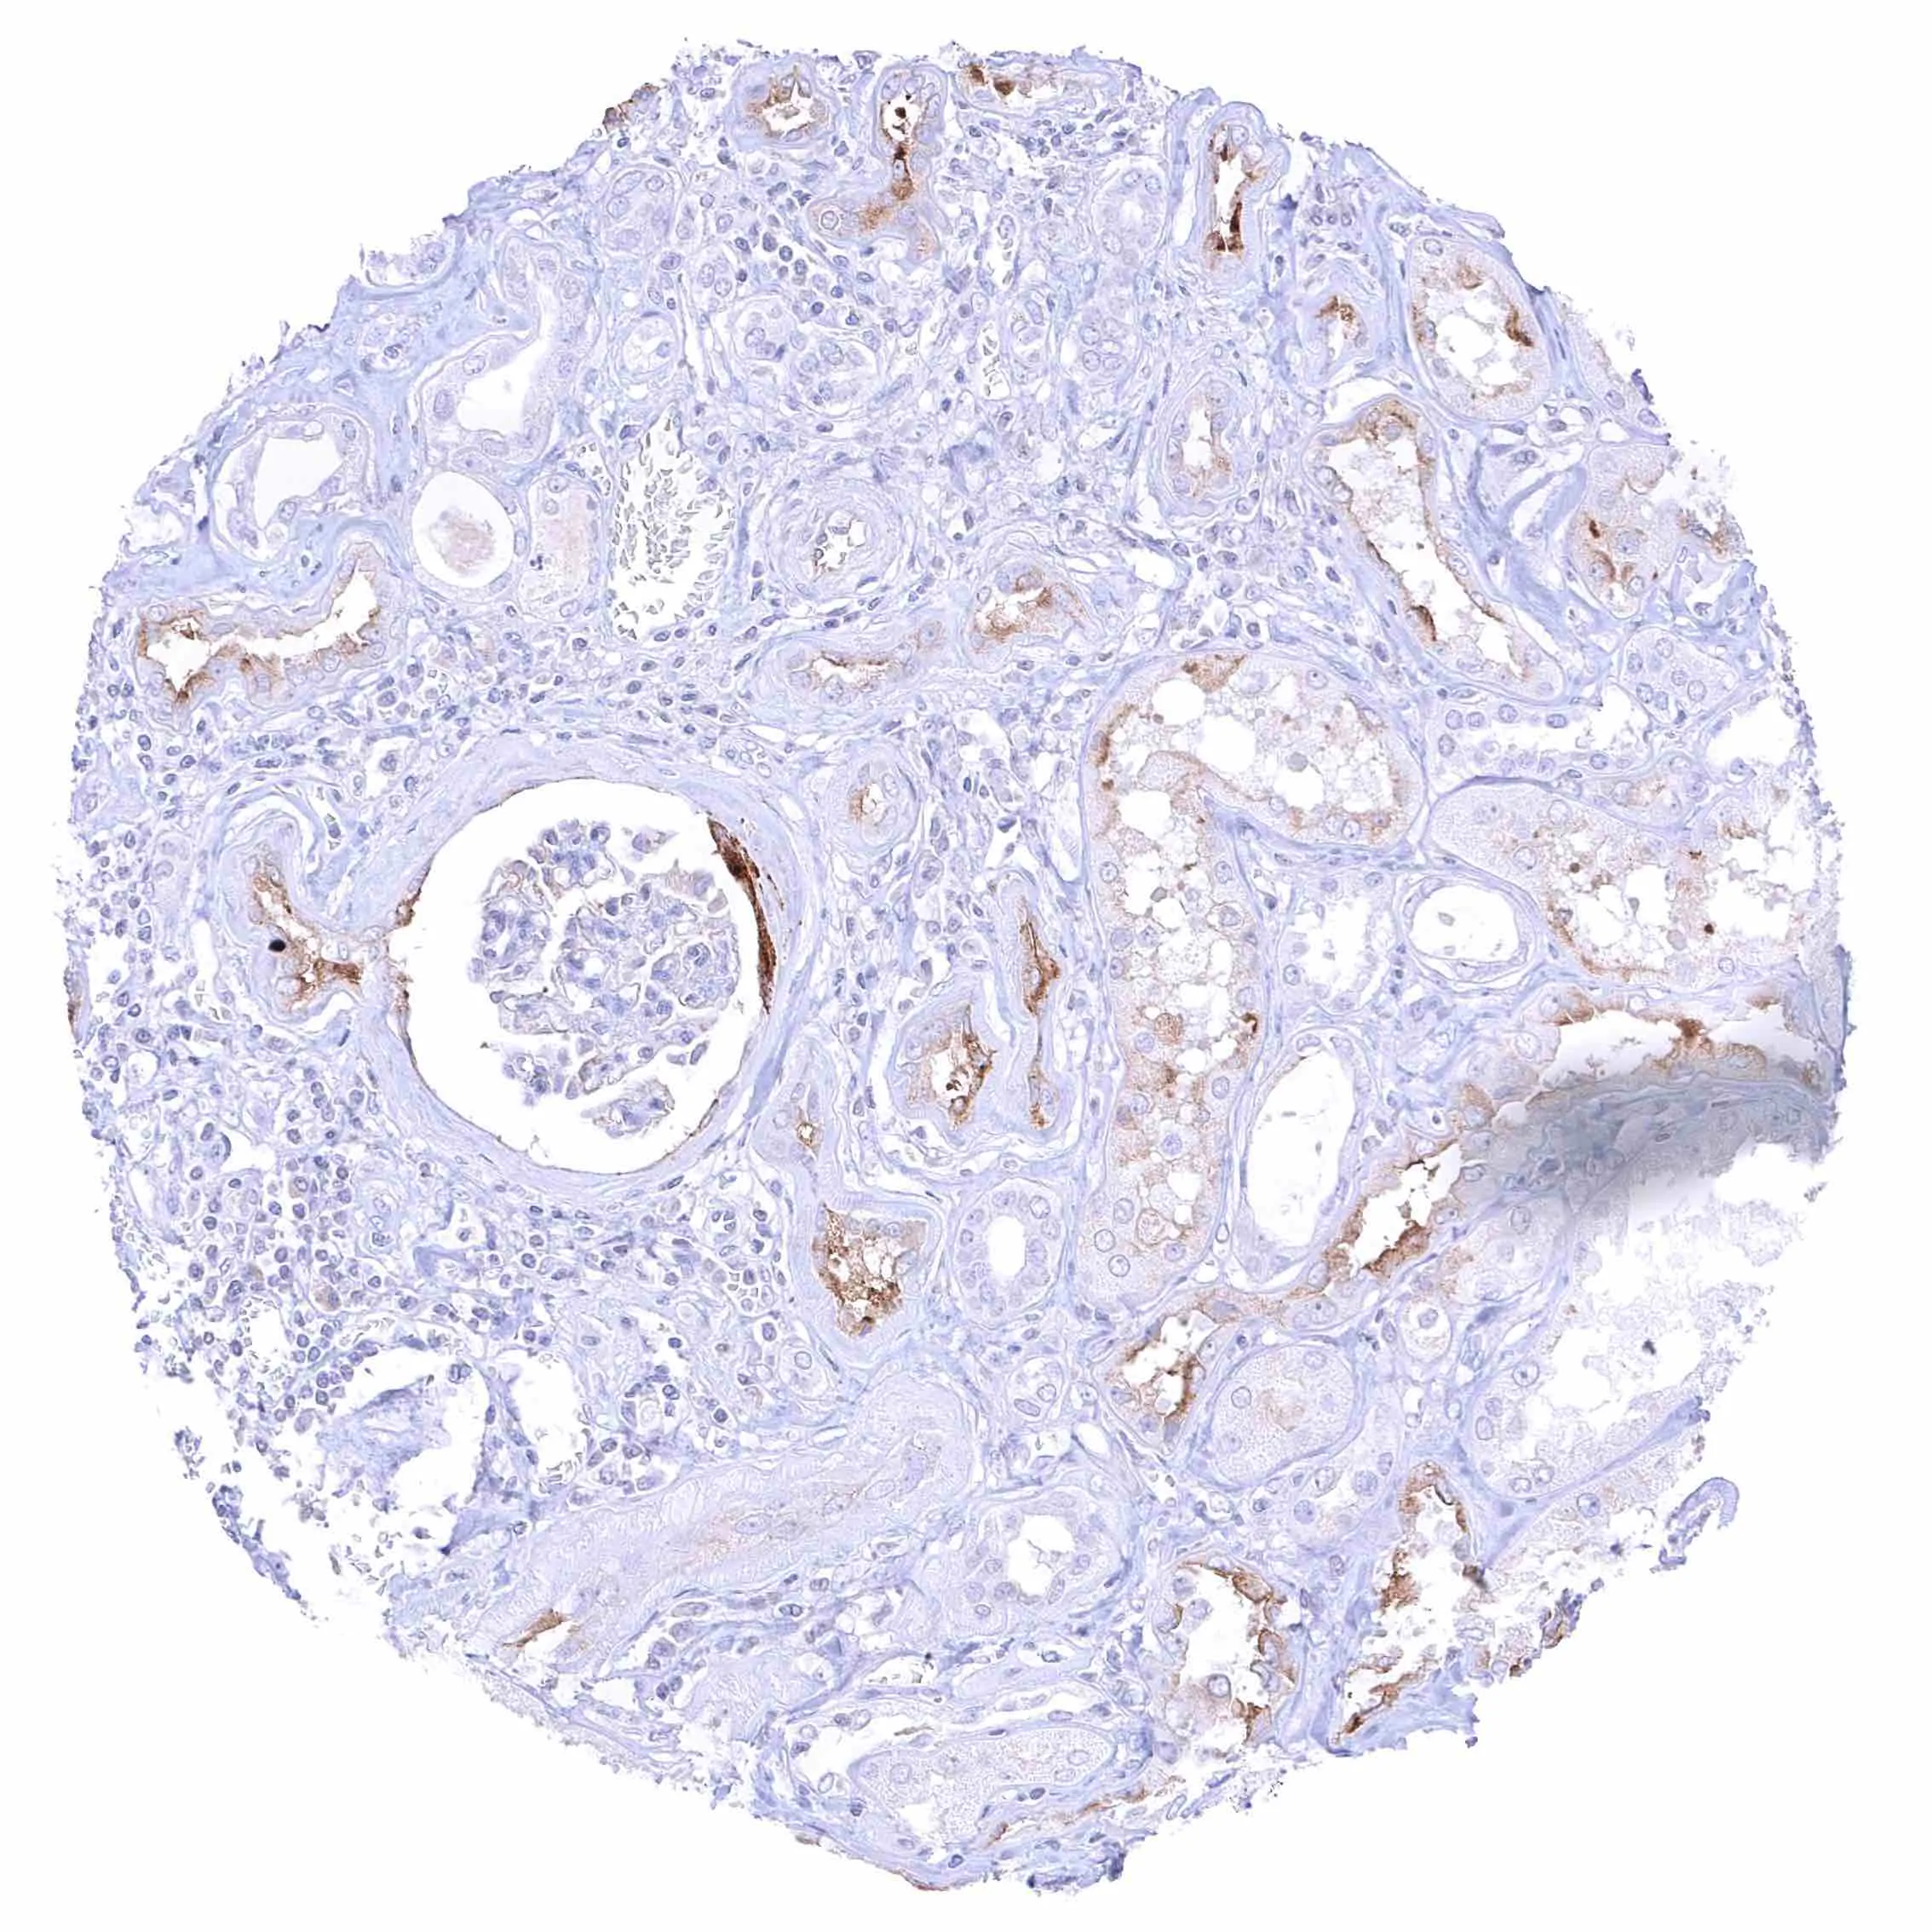

Placenta (chorion) – Distinct membranous and cytoplasmic NPR-C staining of decidua cells.

Placenta, early – Weak NPR-C staining of few endothelial cells.

Placenta, mature – Weak NPR-C staining of few endothelial cells.